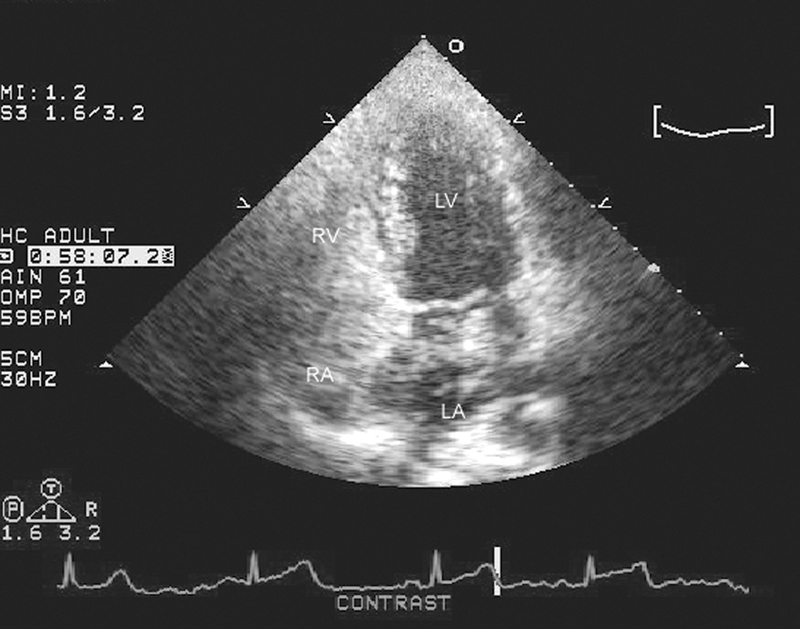

فحوصات تشخيصية لبعض امراض القلب والشرايين التاجية